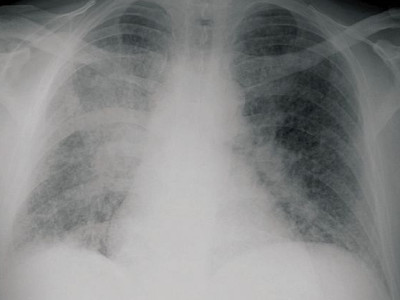

![Blastomycosis Americana (click on photo to enlarge) [source: CDC - Public Domain Image] Blastomycosis Americana](../../../images/north-american-blastomycosis-1z.jpg) |

Blastomycosis Americana |

Foto: CDC Atlanta (Public Domain Image).

X-thorax: Pralay K.

Sarkar (Wikimedia, Creative Commons License

3.0)